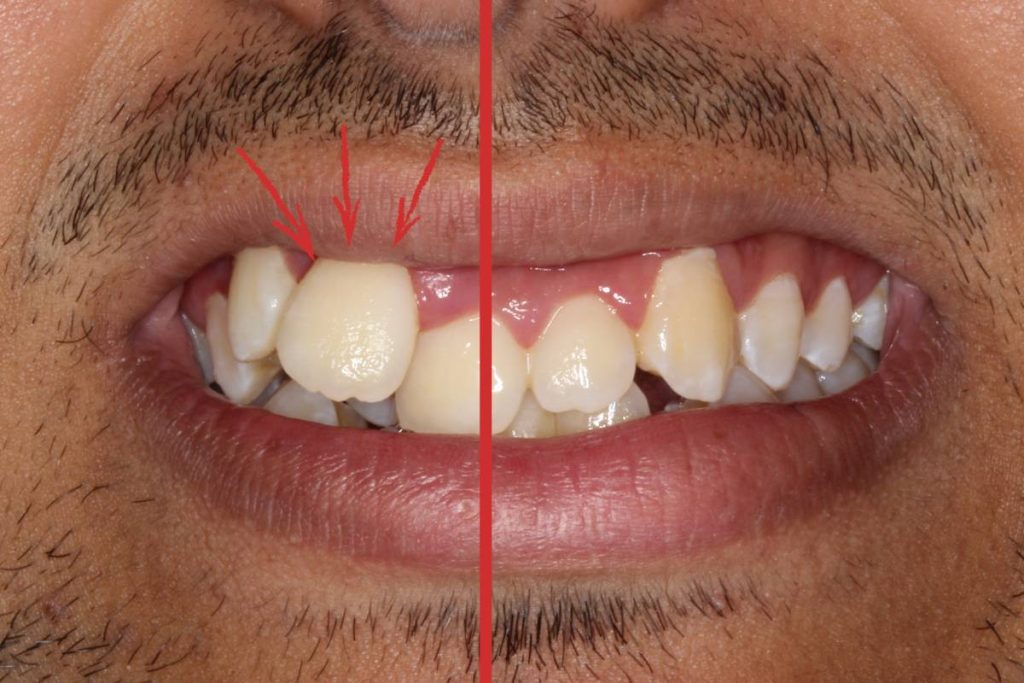

Indicaciones gráficas para una mejor compresión de su situación.

Nuestras sospechas se confirmaban. El caso 139 residente en Torremolinos presentaba 2 circustancias que suelen ser comunes a este tipo de situación aguda y que hacen los tratamientos sean más complejos: macrodoncia generalizada y apiñamiento con asimetría debido a una discrepancia óseo-dentaria. Vamos por partes y explicaremos primero qué significa cada cosa.

Recordamos que el eje que separa ambas mitades estaba desplazado 12 mm hacia la derecha del paciente en la parte superior, mientras que en la arcada inferior la discrepancia era menos, pero al revés.

Si os fijáis, la paleta derecha era (de forma natural) un poco más grande que la de al lado, pero el paciente afirmó que le gustaba esa asimetría y que no quería ningún tipo de talla o intervención en ella. A nosotrxs nos pareció perfecto por que tu boca es única y las singularidades son las que la hace diferente.

Antes y después